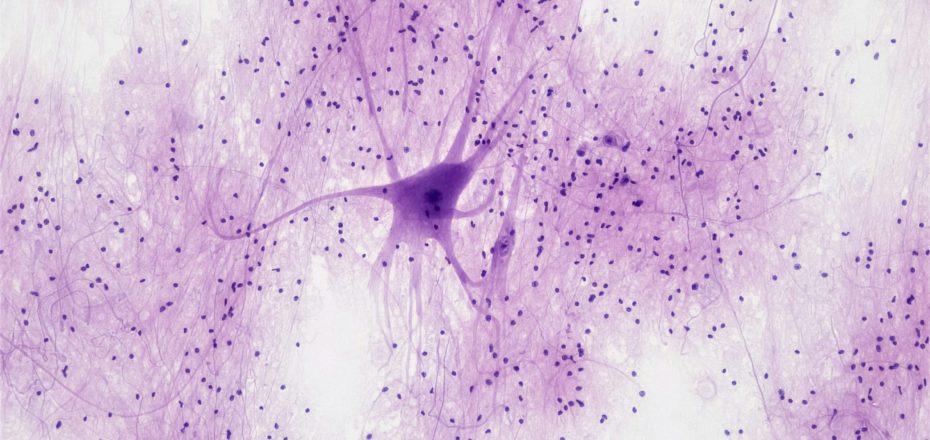

Die BHS besteht aus mehreren zellulären und molekularen Komponenten:

- Kontinuierliches Endothel mit dichten tight junctions: Diese hochspezialisierten Zellen bilden eine dichte Barriere, die nur gezielte Stoffe passieren lässt – dies liegt u.a. am Isotyp der Claudin-Proteine.

- Astrozyten: Diese Gliazellen stabilisieren die BHS, regulieren den Blutfluss und unterstützen die neuronale Funktion. In unseren Tutorien besprechen wir die Funktion der Astrozyten und anderer Gliazellen genauer!

- Perizyten: Sie beeinflussen die Gefäßstabilität und Barriereintegrität.